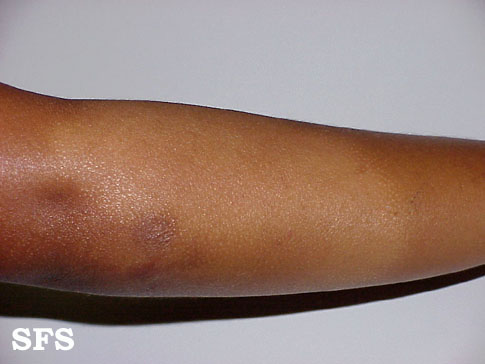

eczematid